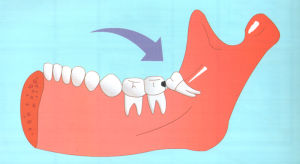

2、長智齒時常因萌出位置不足,可導致智齒萌出不全而異位或阻生,牙冠部分外露於牙齦之外,部分被牙齦覆蓋。

3、由於沒有對咬牙,有時智齒會過度萌發伸長,進而影響咬合;還有時會萌發不足成為阻生齒,引起牙列不齊,冠周間隙感染,張口困難。

4、智齒是第三大臼齒,對相鄰的第二磨牙有重要影響。由於大多數智齒是前傾阻生的,約呈45度角頂在第二磨牙上,從而形成一個牙冠夾角,容易嵌塞食物,久之導致第二磨牙齲壞,甚至牙髓炎,就算沒有那么嚴重也會影響第二磨牙的壽命。